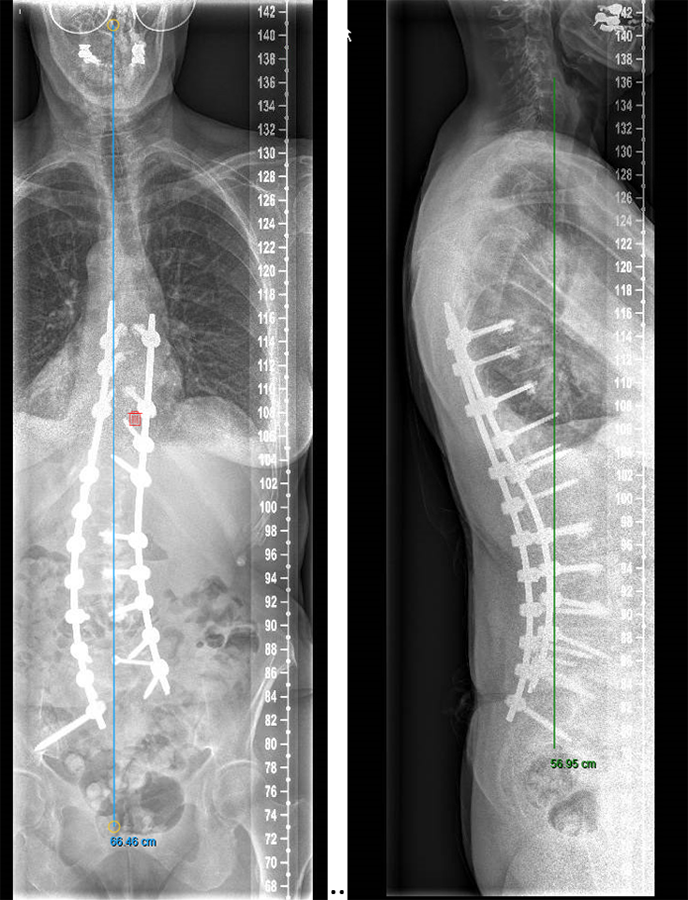

The surgery was planned as a posterior approach to correct the spinal deformity and restore coronal as well as sagittal balance with direct and indirect decompression of the right L3 nerve root. The preoperative bone assessment and DEXA scan indicated osteopenia and considering her medical history the decision was to use cortical fix screws that also allowed cement augmentation.

We performed a posterior fusion and correction of Th8-S2-SI-Ilium (Fig 6). In Th9, Th10, Th11, and Th12 we instrumented only unilateral pedicle screws due to small pedicle diameters. A S2-SI-Ilium screw was placed on the left side. A supplemental translaminar screw was used at L5-S1 on the right side. We augmented the screws in Th8, Th9, Th10, L2, L3, and L4. Additionally, a TLIF approach was performed on L2-3 and L3-4 with autogenous bone as interbody support. No complications occurred during nor after surgery, and she remained in good balance during the 1-year postoperative follow-up.